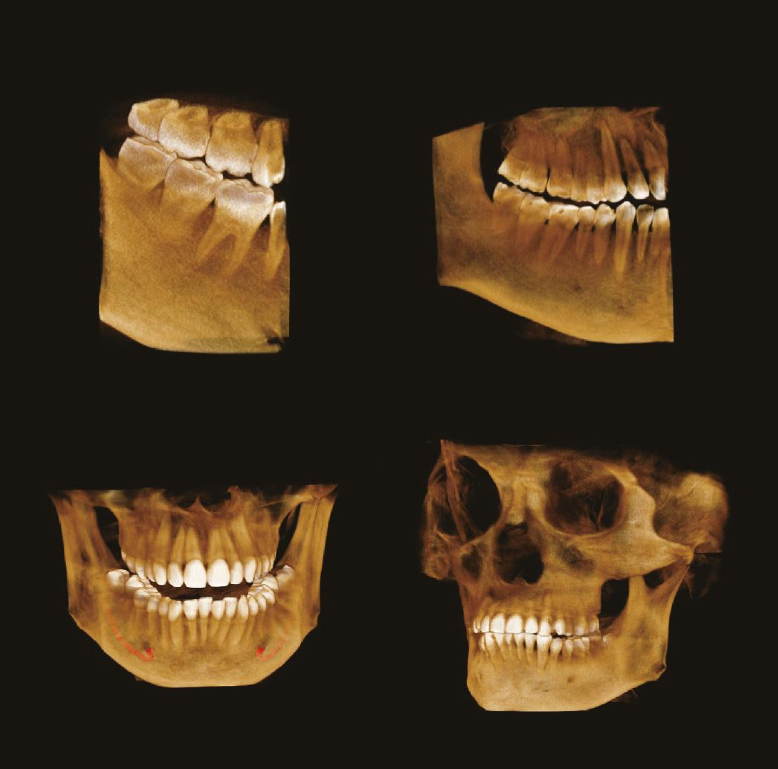

70 мкм в Эндодонтическом режиме 3,5×4 см

Высокотехнологичный детектор с самым высоким разрешением в классе – 70 мкм. Позволяет различить даже самые мелкие анатомические образования и облегчит постановку диагноза в сложных случаях. А вместе с применением алгоритма SMARF инородные тела из металла не испортят качество снимков.

Умная Функция Уменьшения Артефактов от Металла (Smart Metal Artifact Reduction Function) – позволяет минимизировать артефакты от вторичного излучения металлов и получить необходимую диагностическую информацию для постановки корректного диагноза, а также планирования и контроля проведенного лечения.

Устройство оснащено множеством функций, позволяющих проводить качественное и всестороннее обследование. Специально для стоматологов томограф поддерживает эндодонтический режим. Эта функция позволяет делать снимки в разрешении 70 мкм. Снимок получается размером 3,5×4 см. Высокую чувствительность на снимках обеспечивают сенсоры из теллурида кадмия.

Металл больше не помеха

Зачастую частицы металла портят результаты сканирования. Однако с новой технологией SMARF об этой проблеме можно забыть. Умная система убирает помехи от излучения металла, делая картинку четкой и подробной. Благодаря ей у вас на руках будет вся необходимая диагностическая информация.